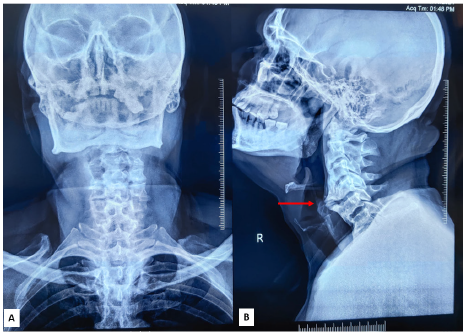

Cervical Osteophyte-Induced Dysphagia: A Case Report

Nongthombam Bidyananda Singh, Manu CB, Suvamoy Chakraborty

Summary

We present the case of a girl in her late teens who presented with a slowly enlarging, painless mass in her

right parotid gland over four years. Initial investigations, including ultrasonography and MRI, suggested a vascular malformation. Fine needle aspiration supported a benign tumour. Histological analysis following excision confirmed the diagnosis of angiomyolipoma (AML) of the parotid gland. This case highlights the importance of considering rare benign mesenchymal tumours like AML in the differential diagnosis of parotid gland masses, even in the absence of typical associations such as tuberous sclerosis.